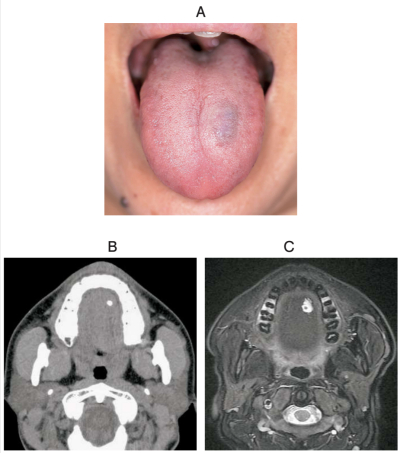

40 歳の女性。舌の腫脹を主訴として来院した。舌背部に弾性軟の無痛性腫脹を認める。初診時の口腔内写真、CT、MRI 脂肪抑制T2 強調像及び口腔内超音波検査の画像を別に示す。考えられるのはどれか。1つ選べ。